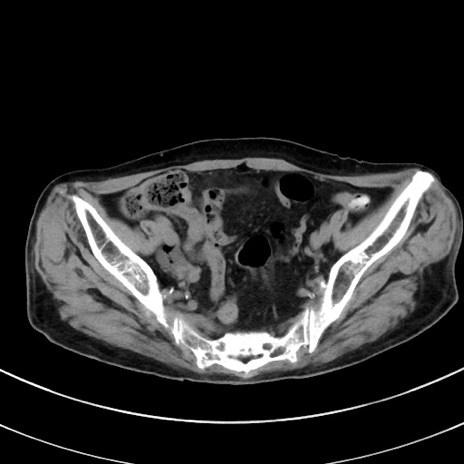

症例33(横断像)

【症例】70歳代 女性

【主訴】心窩部痛

【現病歴】延髄病変の精査・加療にて神経内科入院中。本日より心窩部痛あり。

【身体所見】右下腹部を中心に圧痛と反跳痛あり。